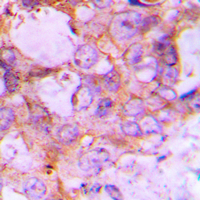

IHC (Immunohiostchemistry)

(Immunohistochemical analysis of Caspase 6 p18 staining in human lung cancer formalin fixed paraffin embedded tissue section. The section was pre-treated using heat mediated antigen retrieval with sodium citrate buffer (pH 6.0). The section was then incubated with the antibody at room temperature and detected using an HRP conjugated compact polymer system. DAB was used as the chromogen. The section was then counterstained with haematoxylin and mounted with DPX.)